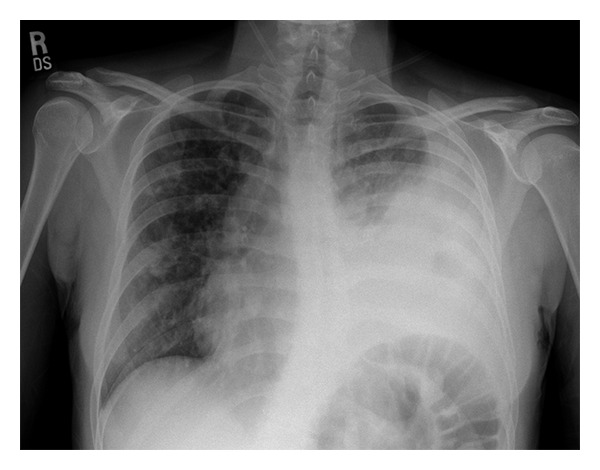

Input 3: What is seen in the X-ray and what should be done?

Image:

• Visual Med-Alpaca: Bilateral infiltrates and bilateral pleural effusion seen in a chest x-ray may indicate a respiratory infection or other respiratory conditions such as pneumonia pulmonary edema, or pleural effusion, it is important to consult a medical professional for a proper diagnosis and treatment plan.

OTHER METHODS

• VQA Medical Model: the decubitus

• Automatic Radiology Report Generation (Image-only): near complete opacification of the left hemi thorax with only a small amount of residual aerated lung in the left upper lobe .

• ChatGPT (GPT-3.5-Turbo) + Automatic Radiology Report Generation (Image-only): Opacification of the lung on an X-ray indicates that there is an abnormality in the lung tissue. In this case, the near-complete opacification of the left hemithorax with only a small amount of residual aerated lung in the left upper lobe suggests that there is likely a significant pathology present in the left lung. Possible causes of this finding include pneumonia, lung abscess, tumor or mass, or pleural effusion (fluid accumulation around the lung). It is important to determine the underlying cause of this finding as soon as possible. A follow-up diagnostic workup may include a CT scan of the chest, sputum culture, bronchoscopy, and/or a biopsy of any suspicious areas in the lung. The appropriate treatment will depend on the underlying cause, but it may include antibiotics, drainage of any fluid collections, or surgery to remove any masses or tumors. Prompt evaluation and treatment are necessary to prevent complications and improve outcomes.